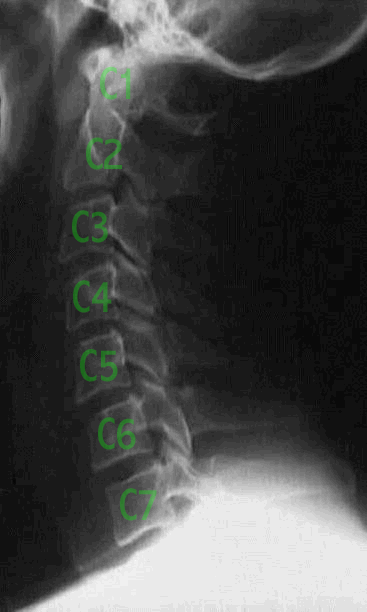

The illustration to the right is of a textbook normal cervical spine. It consists of seven cervical vertebrae and has the normal curve, or 'lordosis'. Lordosis is a medical term derived from the Greek 'lordos', meaning 'bent backwards'. In medical use, it means that the convexity is to the front. In other words, if you were to draw a line through the center of the vertebra starting at C1 and going to C4, as well as a line from C7 to C4, they would converge at a point towards the front in reference to the starting points- C1 and C7. A lordosis, in lay terms, is a curve towards the front.

The darker areas between the vertebrae contain 'discs'. These discs are composed of an outer layer of cartilage, the 'annulus fibrosis', and an inner gel-like substance, called the 'nucleus pulposis'. The discs separate the vertebrae and allow for freedom of motion to exist in the spine. In addition, they act like spongy shock absorbers to reduce the stress of the head on the neck.

Together, the disc and the lordotic curve allow for freedom of motion while reducing the overall stress to the joints of the cervical spine. This is true in all areas of the spine. However, the thoracic area has the opposite type of curve, called a 'kyphosis'. The lumbar spine has a lordosis. The sacrum, made of fused vertebral segments, has a kyphotic shape. Alterations from normal occur regularly due to birth defects, trauma and/or degeneration.